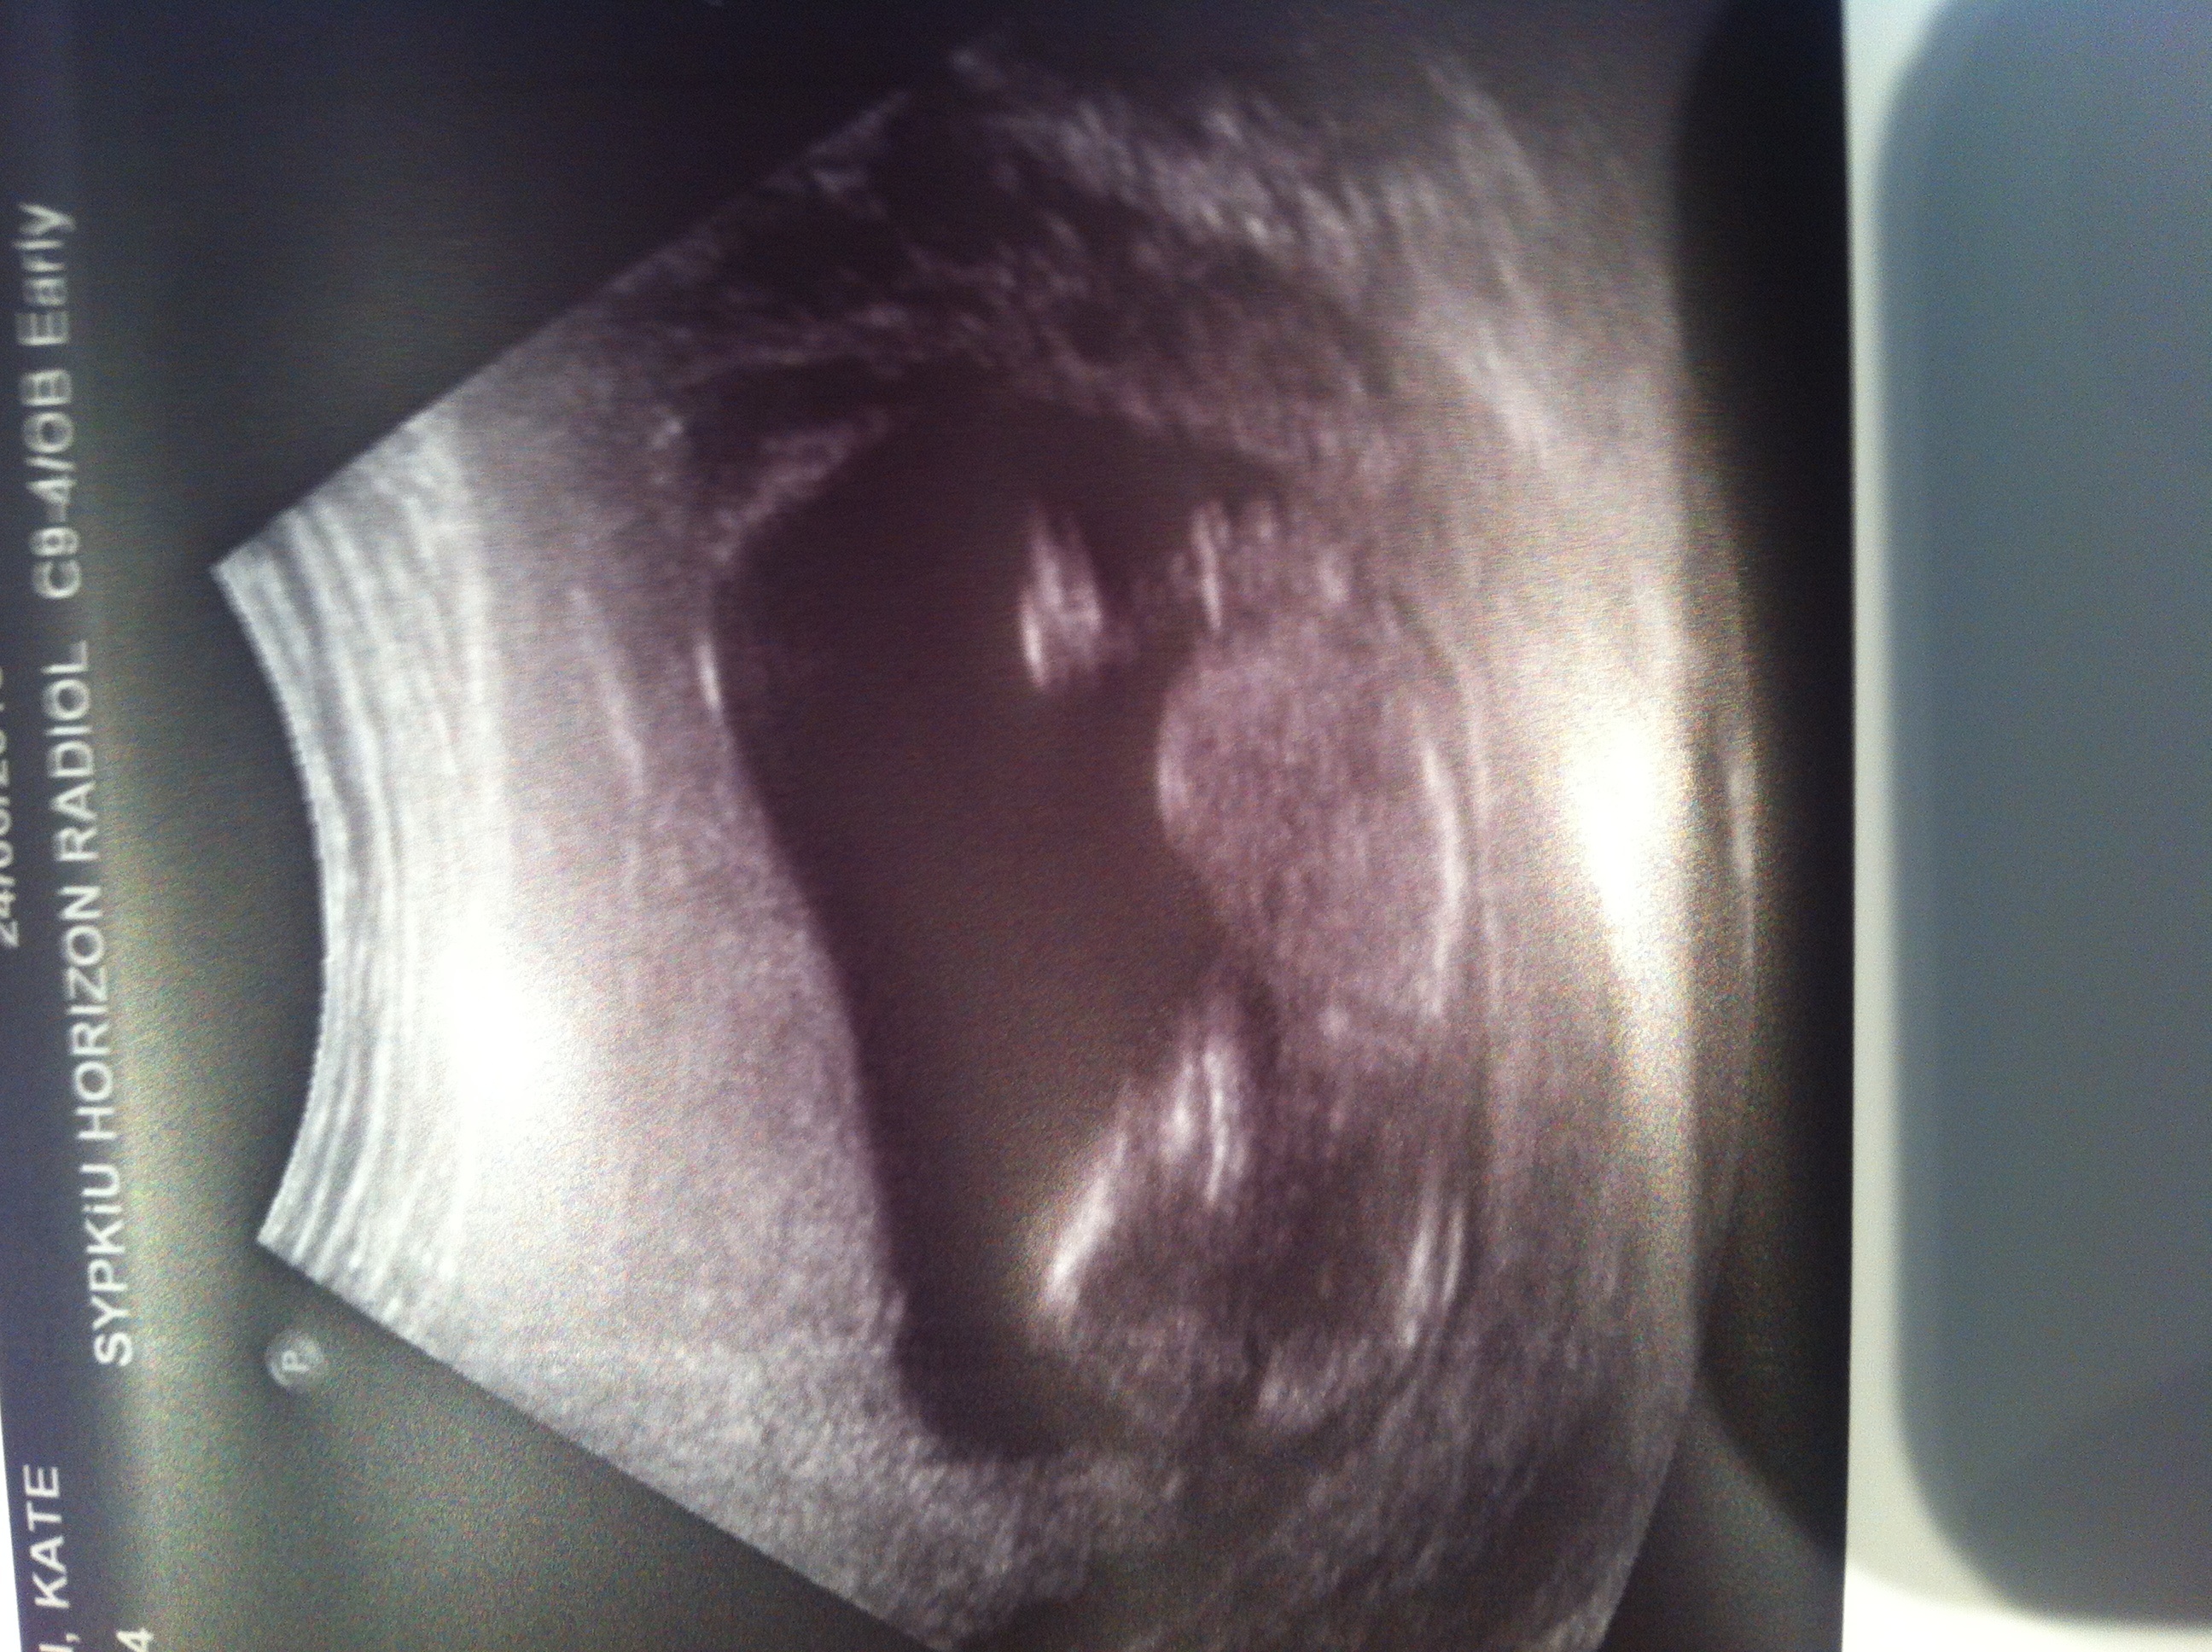

Girl :)

REALLY thinking pink. Would be surprised to hear otherwise :) Congrats!

All three are about as girly as I have seen. Time to prepare for a little lady in your house :)

that's a girl :)